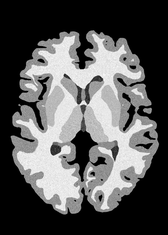

4.2 Registration to a 100 micron ex-vivo brain MRI volume

To showcase the efficacy of our method on real large scale images, we register a 250 in-vivo MRI image (Lüsebrink et al., 2017) to a 100 ex-vivo FLASH human brain volume (Edlow et al., 2019). This represents an inverse problem with more than 11.2B optimizable parameters (compared to 20M for clinical datasets), or 44.8GB of GPU memory. The entire problem does not fit on most GPUs, necessitating distributed multimodal registration. We optimize a composite transform - affine followed by a diffeomorphic mapping; details can be found in Section E.1. Multimodal deformable registration took 58 seconds on 8 NVIDIA A6000 GPUs, which is unprecedented at this resolution. Fig. 6 shows qualitative results, highlighting the ability to register highly detailed structures such as cerebellar white matter; these structures are not visible at macroscopic scales. The resultant advantages of performing registration at this scale can allow researchers to characterize the neuroanatomy at microscopic resolutions and allow morphometric analysis of cortical layers and subcortical nuclei among other structures.